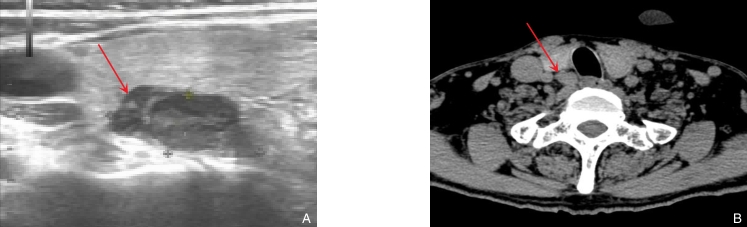

图1 CKD并发SHPT患者影像学特征 A:超声检查提示甲状腺右叶下极背侧后方可疑甲状旁腺(大小约20.0 mm×9.5 mm);B:CT检查提示甲状腺右叶下极背侧后方可疑甲状旁腺(大小约2 cm×1 cm)Fig.1 Imaging characteristics of a patient with CKD and SHPT A: Ultrasound showing a suspicious parathyroid gland located posterior to the lower pole of the right thyroid lobe (approximately 20.0 mm × 9.5 mm); B: CT scan revealing a suspicious parathyroid gland in the same location (approximately 2 cm × 1 cm)